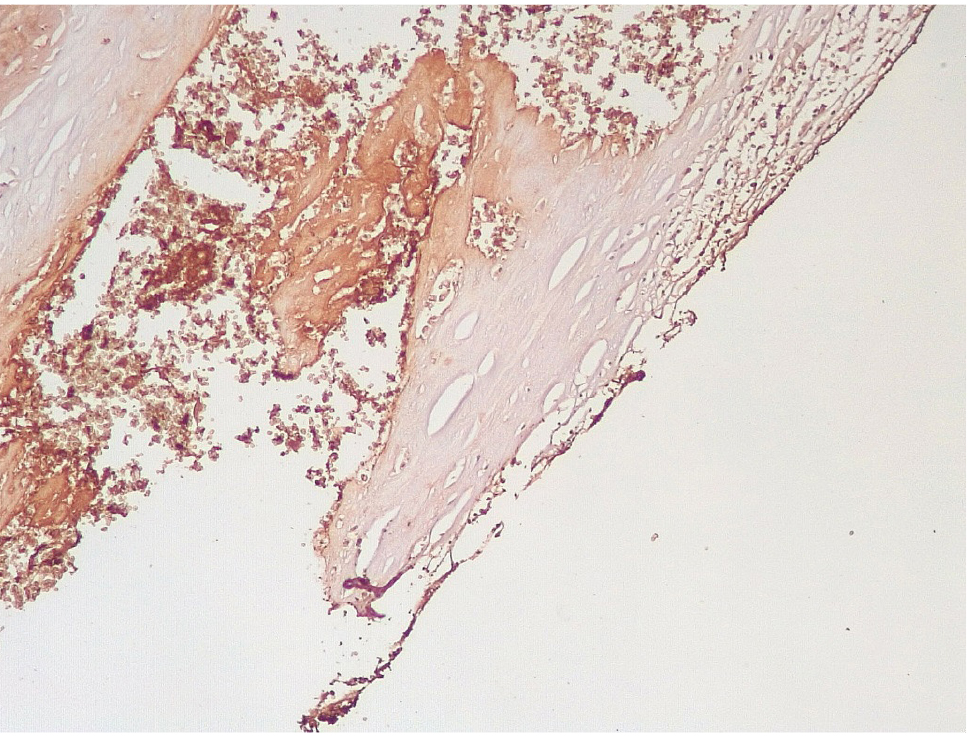

Маркер эндотелиальной дисфункции – фактор Виллебранда (ФВ) ярко экспрессировался в клетках эндотелия КА и субинтимально, что могло свидетельствовать о выраженной дисрегуляции коагуляционных свойств крови (рис. 5). В то же время экспрессия белка CD31 в указанные сроки после стентирования была слабовыраженной, что могло указывать на выраженные дистрофические изменения эндотелиальных клеток КА.

В течение 7–15 суток после стентирования КА наряду с формированием пристеночных фибриновых тромбов с признаками организации в стенках атером наблюдались репаративные процессы, связанные с неоангиогенезом в виде образования мелких тонкостенных кровеносных сосудов капиллярного типа, окруженных мелкими лимфоцитарными, гистиоцитарными клеточными инфильтратами (рис. 6, 7).

Сохранялась резковыраженная яркая экспрессия ФВ как со стороны интимы, так и субинтимально, в участках альтерации атером (рис. 8). В то же время экспрессия белка CD31 была негативной на всем протяжении стенок КА.

Через 3–7 суток и позднее, спустя 7–15 суток после стентирования КА, в просветах КА отмечаются пристеночные смешанные (фибриново-лейкоцитарные), фибриновые тромбы с признаками организации, что сочетается с явлениями неоангиогенеза стенки артерии. Данный патологический процесс ремоделирования стенки КА после стентирования может отражать, с одной стороны, необратимые повреждения клеток эндотелия, ведущие к микротромбообразованию, а с другой – отражать репаративные процессы в исходе воспаления.

Позднее, спустя 3–7 суток, возникают пристеночные смешанные тромбы, которые через 7–15 суток имеют признаки организации, что сопровождается резкой яркой экспрессией белка фактора Виллебранда.